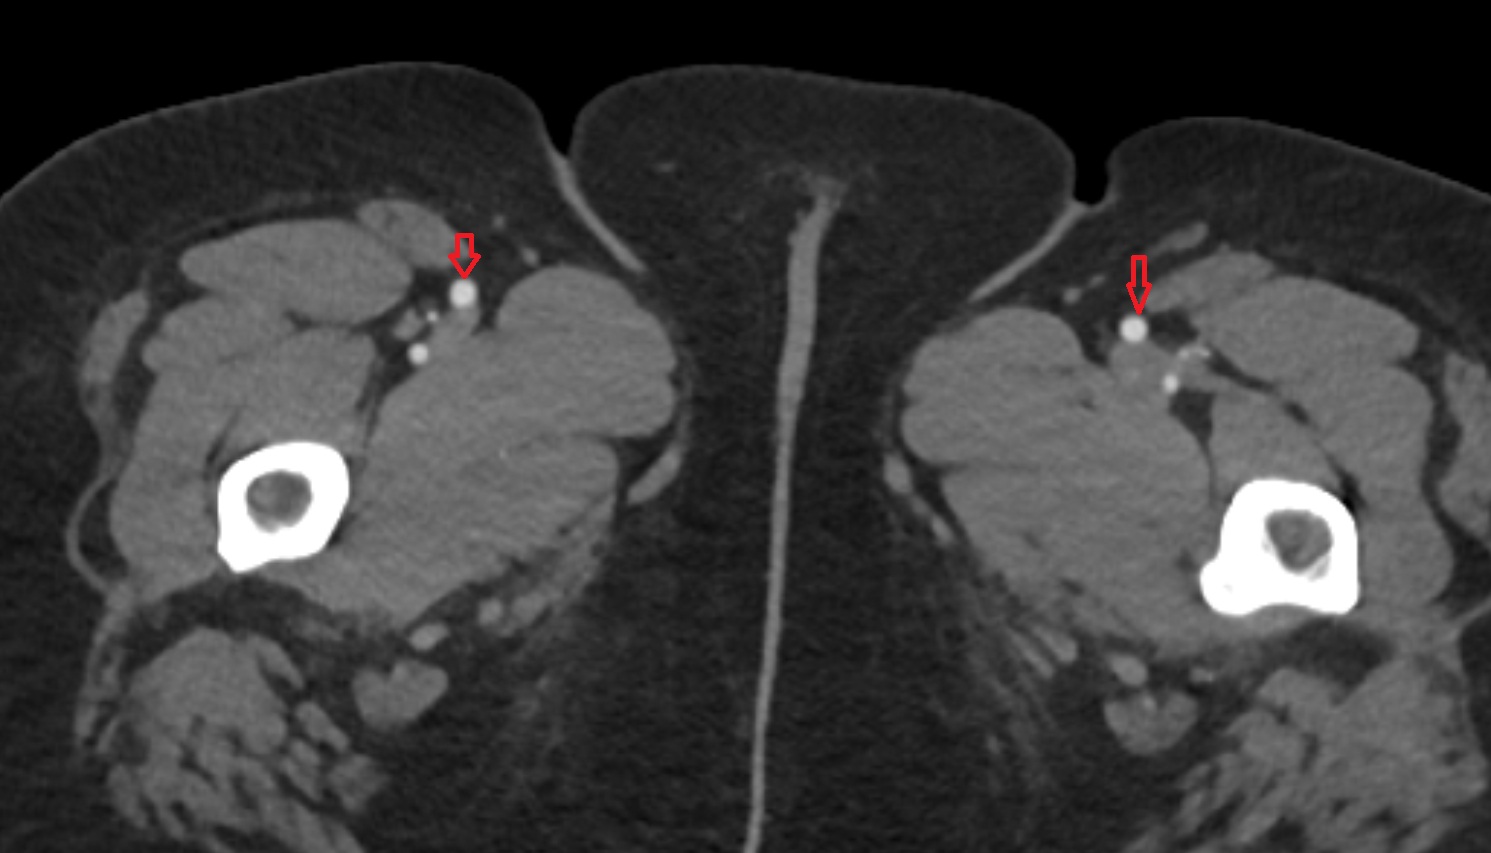

- Deep femoral artery (profunda femoris)

- Femoral artery

- Superficial femoral artery

- Lateral circumflex femoral artery

- Medial circumflex femoral artery

- Deep femoral vein (profunda femoris vein)